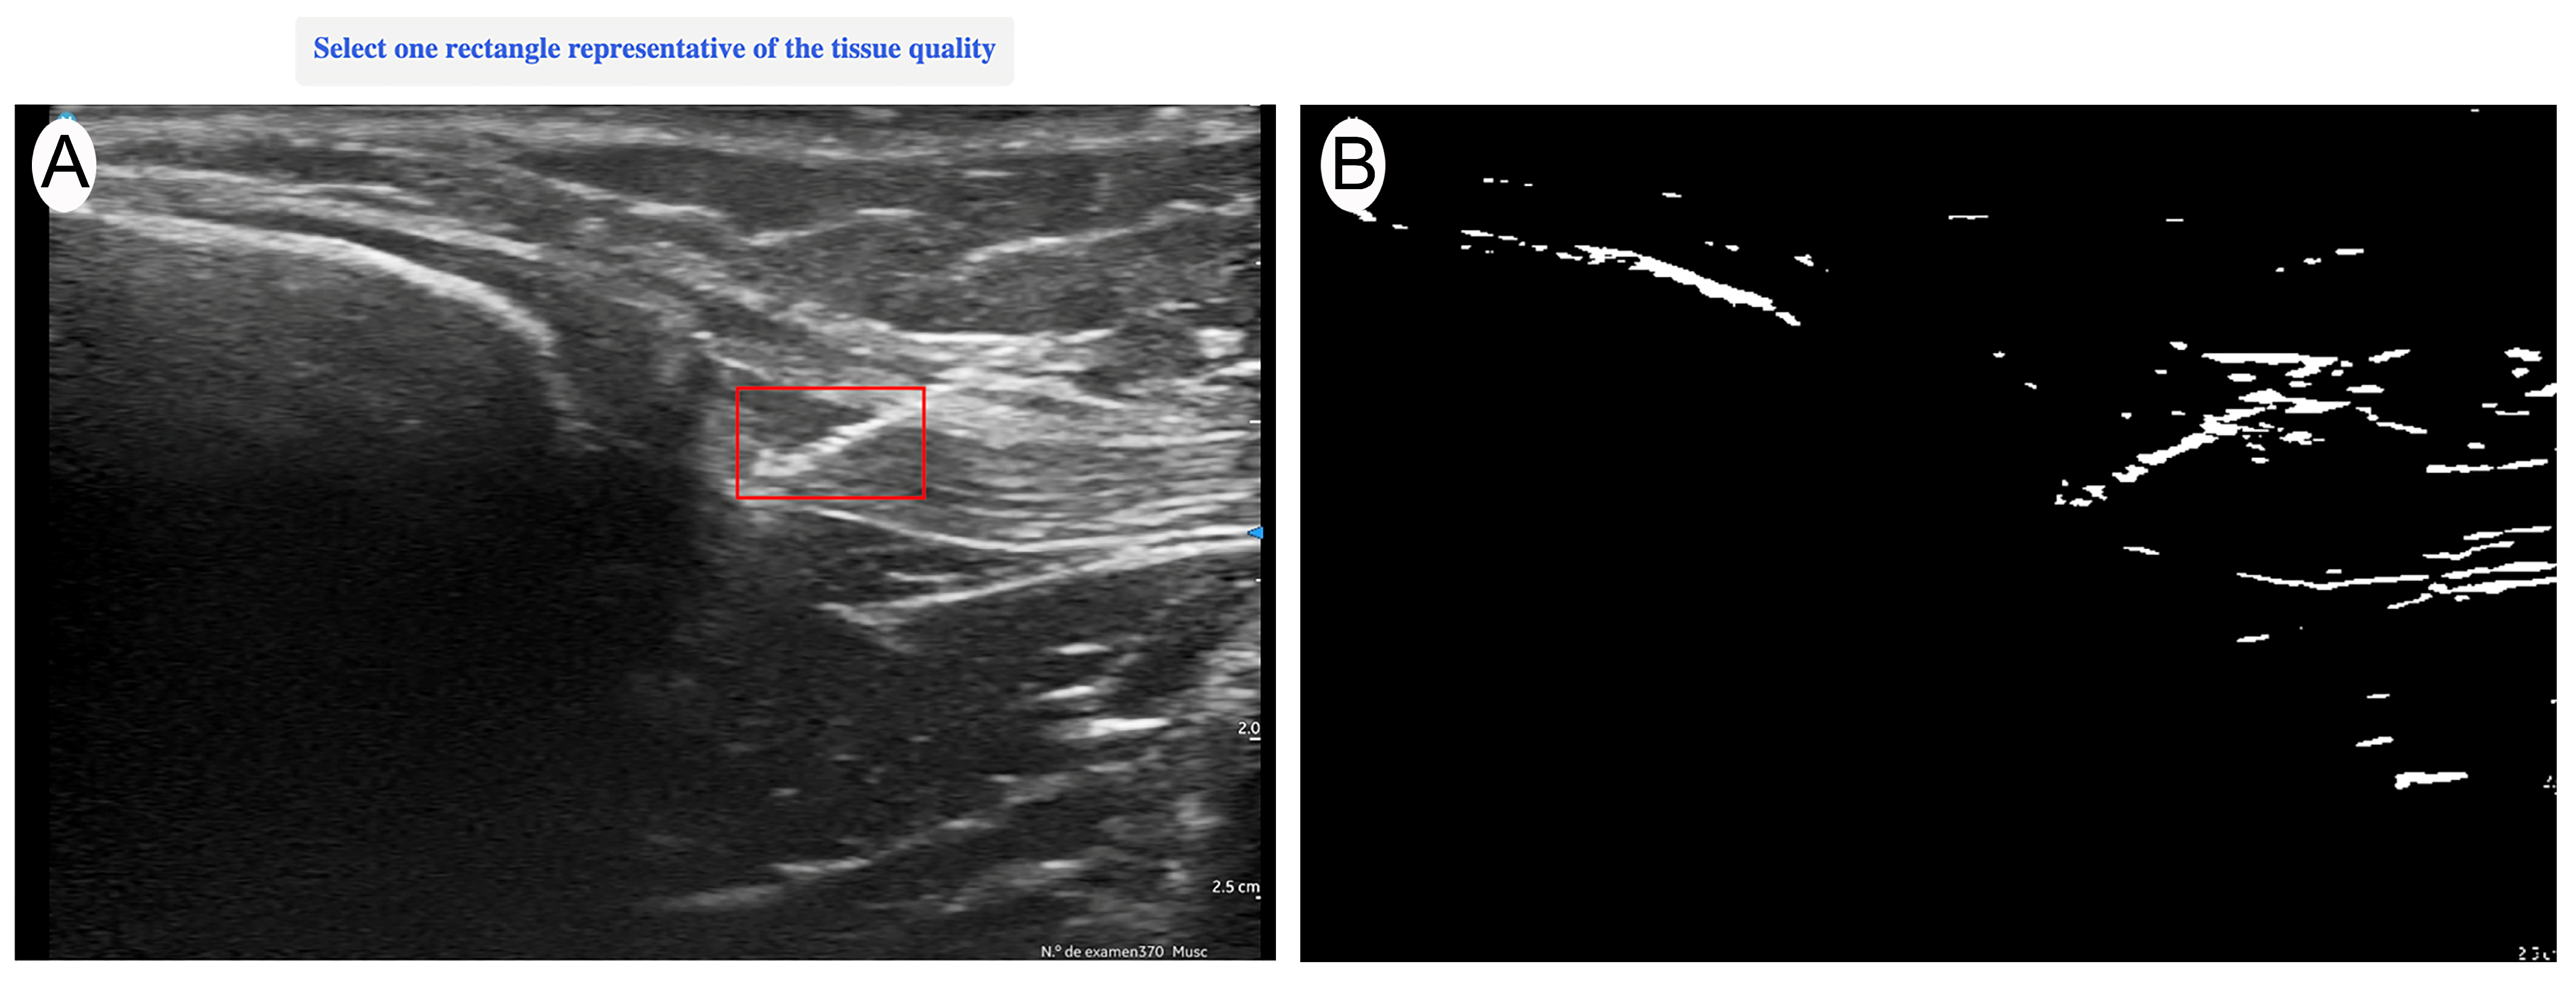

Ultrasound evaluation was performed with a Vscan portable ultrasound system (General Electric, Boston, MA, USA) immediately after each current application. Imaging was conducted in a longitudinal in-plane view, selecting the best available image that optimally represented the treated area. The evaluation was carried out by an expert with more than 15 years of experience in musculoskeletal (MSK) ultrasound, ensuring an accurate and reproducible assessment of structural changes. The ultrasound evaluator was blinded to the intensity applied to each sample to ensure unbiased image analysis. After the intervention was applied, the needle was temporarily left in place to allow the blinded evaluator to identify the treated area. Once the region of interest (ROI) was manually marked—encompassing the full extent of the needle’s trajectory from the first to the last visible point of the needle within the tendon—the needle was then removed, and quantitative analysis was performed on the selected image (Figure 1). The acquired images were quantitatively analyzed using UZ eDosifier, an adaptation of UZ qTool software [10], specifically developed to assess the echogenic effects of electrolysis on tendon tissue (Figure 2). The development of this tool and its quantitative image-processing workflow have previously been described in detail. This software enables objective image-based measurements, providing information on ultrasonographic characteristics following current application. In this processing step, a standardized global thresholding procedure was applied across all images, using a fixed intensity threshold value of 150 greyscale units, to consistently delineate hyperechoic regions generated by the electrolysis application. This fixed threshold was empirically determined during the software development phase to optimize sensitivity and specificity in detecting gas-related echogenic changes. Table 1 presents the quantified variables. The combination of these measurements enables a quantitative assessment of electrolysis effects on tendon tissue, supporting the identification of response patterns and potential dosage thresholds.

Figure 2. (A) Region of interest (ROI) selection. (B) Quantitative transformation using UZ eDosifier software to assess the echogenic effects of percutaneous electrolysis.